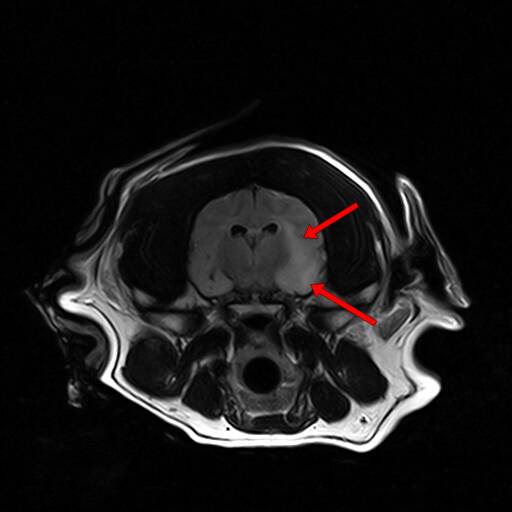

脊髓炎(图一) 脊髓炎(图二)